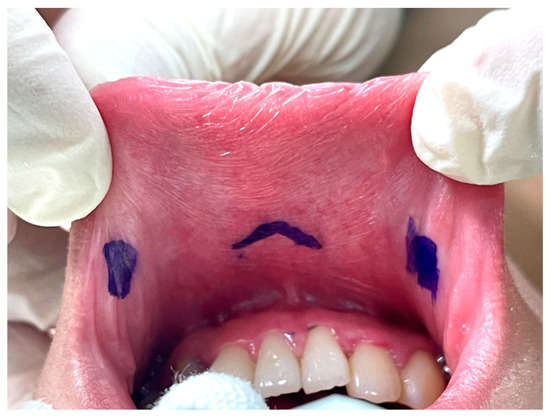

The key point of the incision design in transoral thyroidectomy is to avoid injury to the mental nerve, which might impair the sensation of the lower lip and chin [26]. In keeping with anatomical studies of the mental nerve, we adopted the concept of a safety triangle [11,27,28]. A 1.5–2-cm inverted-V shape incision was made just above the labial frenulum in the central location to avoid injury to the medial branch of the mental nerve (Figure 2) [11]. Another option is to make the central incision vertically [29]. Peng et al. [30] suggested wide mucosal dissection to fully expose the ramifications of the mental nerve and determine the optimal site for trocar insertion. Yeh et al. [31] used computed tomography simulation and 3D printing techniques to create a module that marks the location of the mental foramen and thus guides the surgeons to avoid mental nerve injury.

Vestibular incision design in transoral thyroidectomy.

The other two lateral incisions (0.5 cm) were made close to the inner edge of the bilateral mouth commissure [5,32].